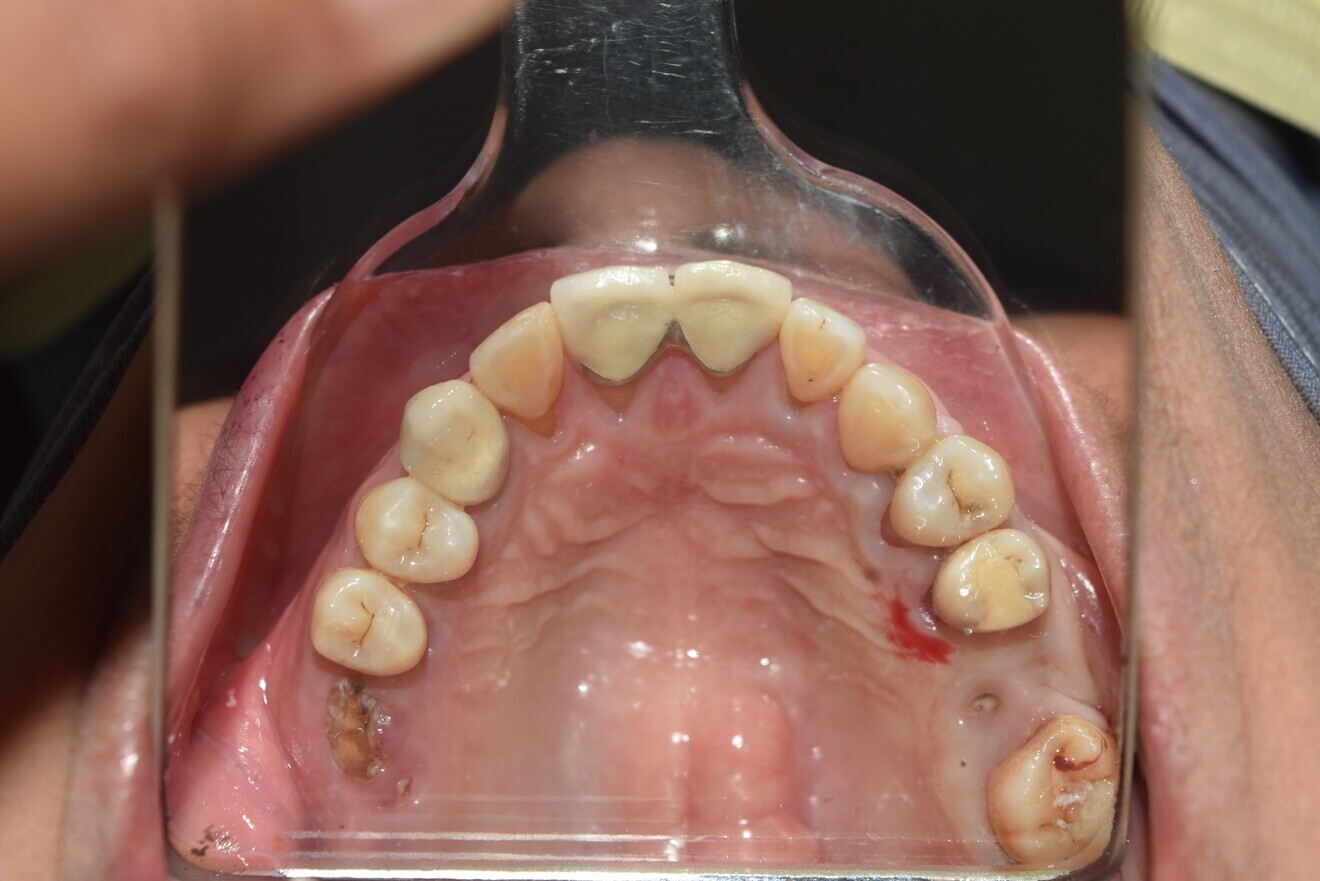

Case 2

• 50-year-old woman

• No underlying medical condition.

• Main complaint: Multiple gaps.

Intra-oral findings:

Class I malocclusion with poli diastemas in both upper and lower arch.

Overbite= 1mm Overjet = 3mm

No molar classification (absence of molars)

Class I canine on right and left side.

Upper midline (mesial to 11) on with face.

Lower midline on with the chin.

Panoramic radiograph analysis:

Missing 18, 16, 25,26, 28, 36, 47 and 48.

20-30% vertical bone loss upper anterior region.